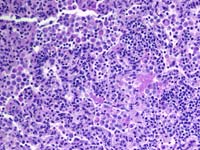

Figura 1: Pneumonia por Pneumocystis carinii  Figura 2: Vesícula biliar num caso de Peste Suína Africana  Figura 3: Pulmões de um caso de Peste Suína Clássica Figura 3: Pulmões de um caso de Peste Suína Clássica Figura 4: Rinite grave num caso de Doença de Aujeszky  Figura 5: Gânglios linfáticos traqueobronquiais entumescidos num caso de PCV2  Figura 6: Pulmões de um caso de gripe suína |

Em primeiro lugar, relativamente aos casos exóticos, todos tratamos de os manter à margem. São um rotundo fracasso, prova disso são a Febre Aftosa (FA) no Reino Unido, ou a Rússia com a Peste Suína Africana (fig. 2) ou em alguns casos somos nós que os geramos, como por exemplo, no Reino Unido com a FA. A Peste Suína Clássica continua a reaparecer no Centro e no Leste da Europa, Alemanha, Hungria e Rússia (fig. 3). A doença de Aujeszky reapareceu recentemente na Roménia (fig. 4) e a Doença Vesicular em Portugal. Por agora não sabemos nada sobre a distribuição dos novos vírus, como o da hepatite E pela Europa ainda sabemos que existe em Espanha e no Reino Unido, mas sem associações definitivas com vírus similares em humanos de modo que até agora não se confirmou uma zoonose.